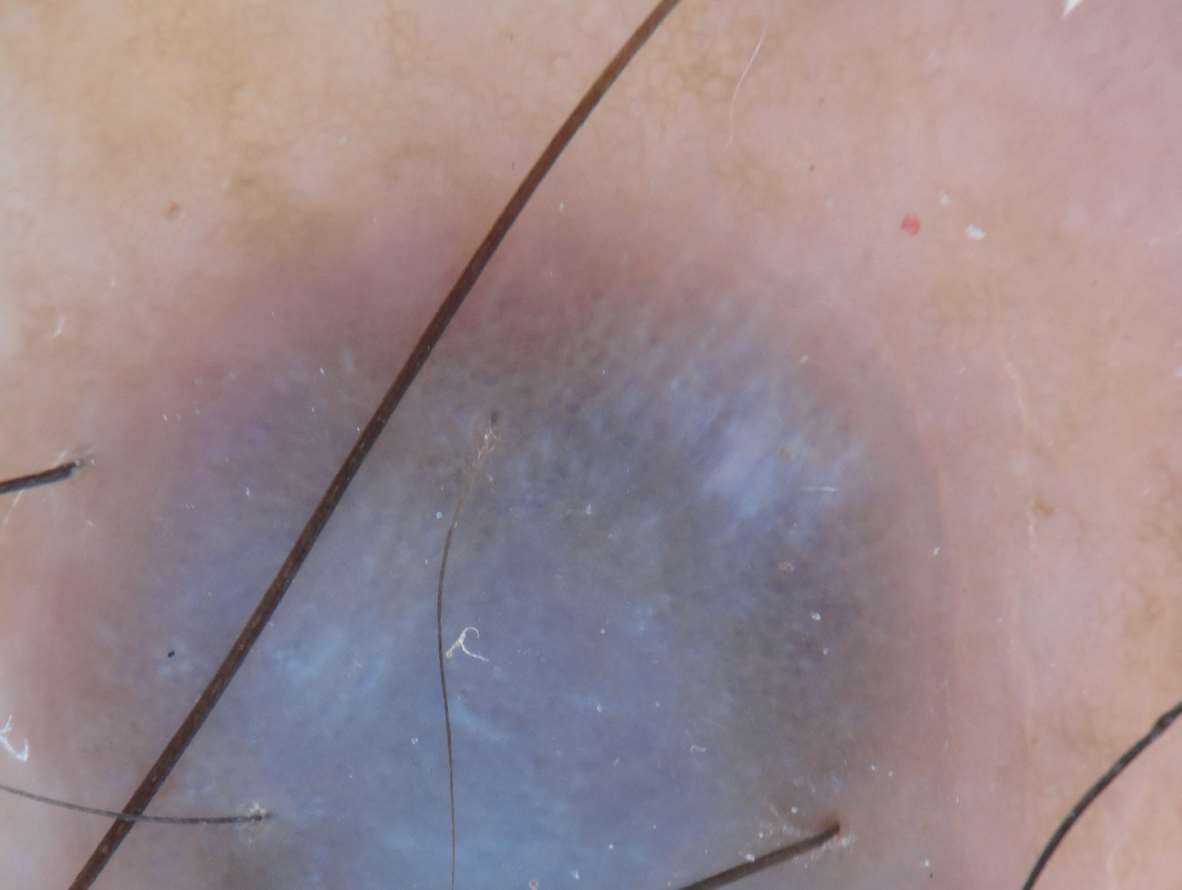

蓝白幕(blue-white veil)是指片状融合的不规则、无结构的蓝色色素沉着,被覆白色“毛玻璃”样、云雾状结构(图1-6)。组织学上对应于色素细胞或色素在真皮的浓集,同时伴有致密的正角化过度。蓝白幕是黑素瘤重要的皮肤镜特征。

图1-6 恶性黑素瘤患者肢端皮损的皮肤镜下蓝白幕征象